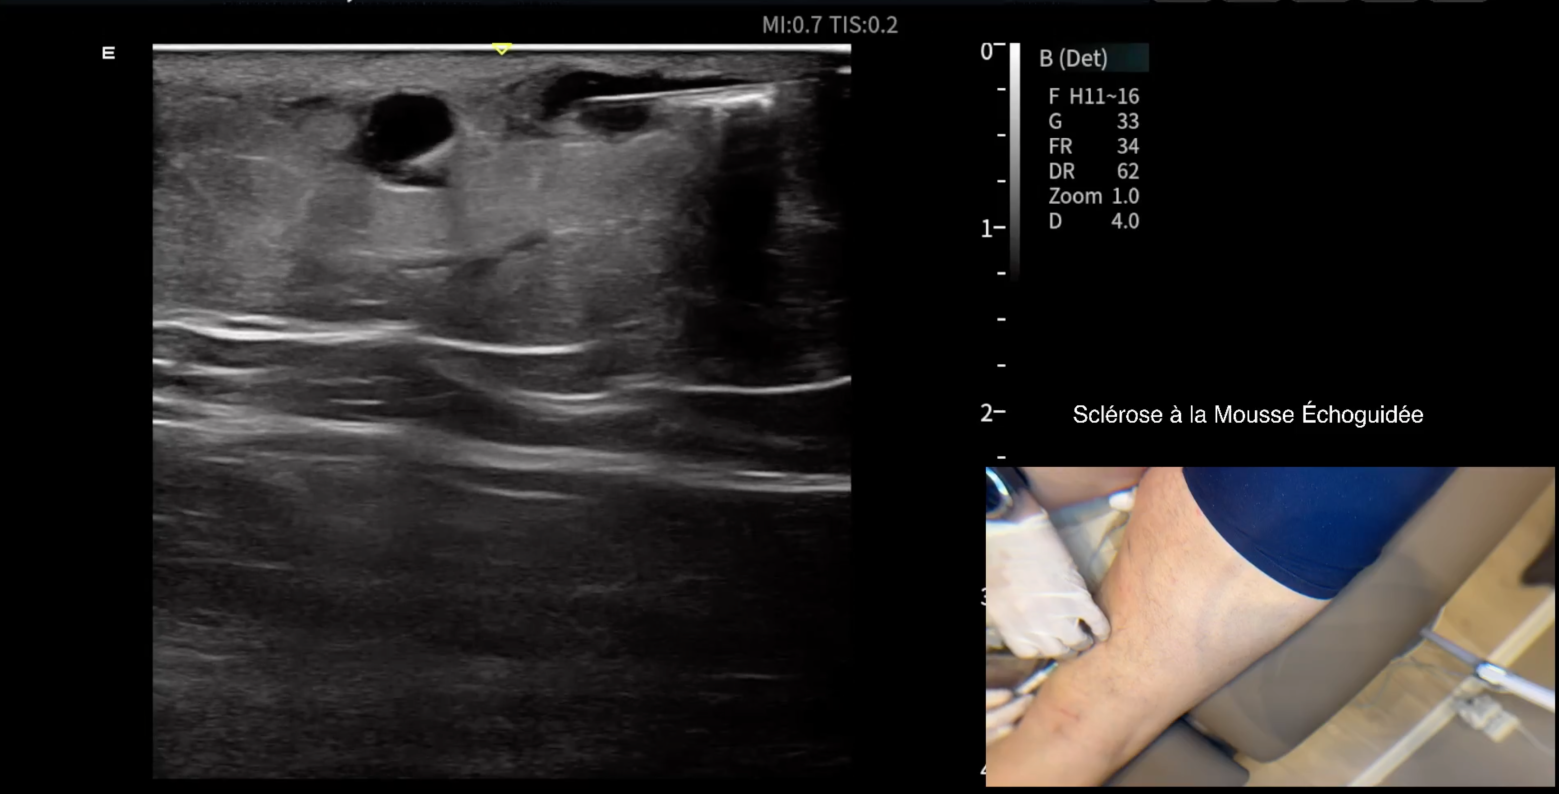

Cette méthode utilise l'échographie pour guider l'injection de mousse sclérosante. Elle permet de cibler précisément la source du reflux sanguin. La mousse repousse la colonne sanguine et favorise le contact entre l'agent sclérosant et l'intérieur du vaisseau afin d'éliminer la varice.